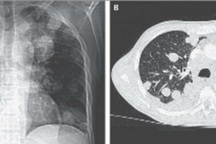

Khoảng 2-3% chửa trứng trở thành ung thư nhau thai, bệnh phát triển nhanh, lan rộng, di chuyển tới các nơi khác như: gan, phổinão… gọi là di căn. Phụ nữ trên 40 tuổi và dưới 20 tuổi có nguy cơ mắc bệnh cao gấp 5 lần so nhóm tuổi khác.

Các trường hợp cường tuyến giáp như: run tay, đổ mồ hôi, giảm cân, nhịp tim nhanh. Các trường hợp chửa trứng thâm nhập có thể gây tổn thương qua lớp cơ tử cung gây chảy máu âm đạo trong ổ bụng. Khi ở giai đoạn muộn, bệnh nhân có thể có các triệu chứng của bệnh di căn: Khó thở, đau tức hạ sườn phải (di căn gan), chảy máu trong ổ bụng, viêm phúc mạc, các triệu chứng tăng áp lực nội sọ, liệt, co giật…